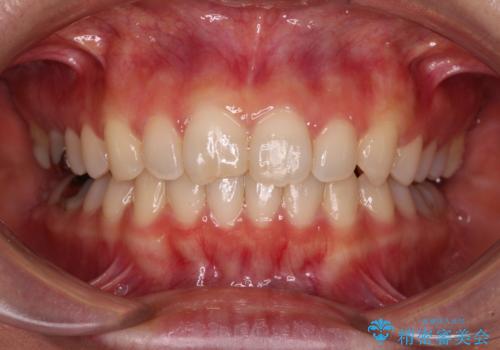

- 近々転勤の予定があるが、早めにインビザラインによる矯正治療を始めたいとのことで来院された患者様です。

上下ともにデコボコの程度は著しいものではなく、インビザラインで十分に対応可能な歯列不正でした。

後戻りによりスペースができてしまうことを避ける目的で、IPR(歯と歯の間を削る)を極力用いない矯正治療を行うこととしました。